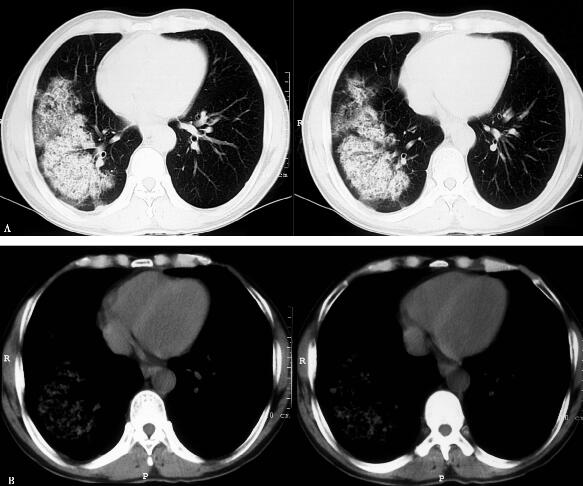

5.胸部影像学:

右肺大片斑片影(图1 A肺窗,B纵隔窗)。

图1

胸部影像学示右肺大片斑片影;血常规示中性粒细胞百分比增高,CRP、PCT明显增高、尿常规示高倍镜下白细胞、红细胞都明显增高。结合患者的病史和体格检查结果,进一步支持感染性疾病——社区获得性肺炎、泌尿系感染的诊断。考虑红细胞及尿蛋白异常与泌尿系感染有关,进一步完善痰培养、尿培养等相关病原微生物学检查,患者目前肾功能异常,考虑患者存在重症感染,累及肾脏所致。

患者拟诊为社区获得性肺炎,经抗感染治疗后感染症状及相关化验较前好转,但胸部影像学较前进展,咯血量增多,同时贫血加重,肾功能进行性恶化。这使我们产生这样的疑问:为何感染已控制但胸部影像学却有所进展?患者为何仍不断咯血,且量较前增多,尿中持续存在红细胞,贫血,肾功能恶化及胸部影像学短期内进展,应注意是否存在ANCA相关血管炎或肺出血-肾炎综合征的可能。

患者为中年男性,慢性咳嗽、咳痰及间断咯血,近1周发热,无鼻窦炎的病史,无双手指间关节的疼痛,无口腔溃疡,无口眼干涩等风湿系统疾病的临床表现,既往无粉尘接触史,无其他肺部疾病史。胸部查体时的右肺下湿啰音为细小水泡音,更接近于帛裂音。辅助检查:胸部CT示双肺斑片影,且短期内迅速进展,血常规示小细胞低色素贫血,尿常规示高倍镜下红细胞、尿蛋白持续偏高,肾功能进行性恶化,血气示氧分压进行性下降。

结合上述资料,考虑患者为肺出血-肾炎综合征或ANCA相关血管炎的可能性大,胸部影像学改变考虑为肺出血-肾炎综合征或ANCA相关血管炎的肺部表现。进一步完善:①抗核抗体系列、ANCA明确是否有ANCA相关血管炎等相关风湿免疫系统疾病;②抗肾小球基底膜抗体测定,明确是否有肺出血-肾炎综合征;③完善鼻窦CT及四肢肌电图明确是否有鼻部及肌肉神经传导受累(ANCA相关血管炎易累及鼻部及肌肉神经);④肾穿刺行肾活检组织检查,病理能明确肾脏受累的具体病因。结果:抗肾小球基底膜抗体阳性,肾穿刺示肾小球囊上皮可见新月体形成,证实了肺出血-肾炎综合征的诊断。